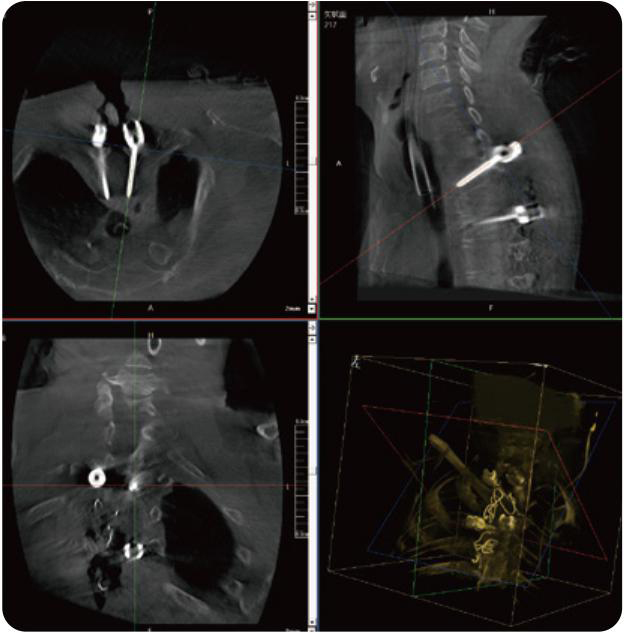

PL300B可應(yīng)用于多節(jié)段脊柱外科手術(shù),輔助醫(yī)生定位病灶部位,為脊柱外科手術(shù)(經(jīng)皮椎體成形術(shù)、椎弓根螺釘內(nèi)固定術(shù)等術(shù)式)提供術(shù)前手術(shù)流程規(guī)劃、入釘位置、角度可視化引導(dǎo),模擬仿真入釘輔助。

PL300B搭配普愛醫(yī)療自主研發(fā)生產(chǎn)的平板3D C形臂,借助一體化自適應(yīng)配準( 軌跡配準)技術(shù),通過追蹤C形臂三維采集軌跡,自動完成圖像坐標建立和系統(tǒng)坐標配準。配準精度更高,操作步驟少,系統(tǒng)運作效率高。